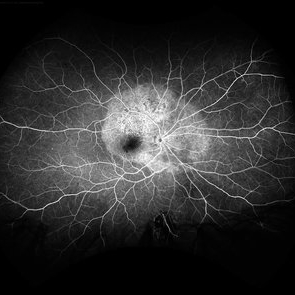

Acute Syphilitic Posterior Placoid Chorioretinitis

May 4 2021 by RAFAEL REIS PEREIRA, MD

A 31-year-old patient with a complaint of photophobia and low visual acuity OD in the previous three weeks. BCVA was 20/60 and 20/20 The fundus examination revealed a placoid white lesion in the posterior pole and vitreous cells in the right eye. The left eye was unremarkable. Fluorescein angiography reveals hyperfluorescent plaque with distinctive “leopard spots” hypofluorescence.

Imaging device: Opto California

Condition/keywords: acute syphilitic posterior placoid chorioretinitis